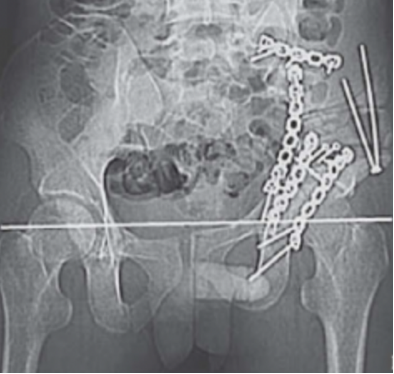

遂行左侧髂骨截骨重建钢板内固定,术后双下肢不等长减少到1 cm,X线检查显示双侧大粗隆大致在同一水平(图3)。

图3(图源:作者提供)